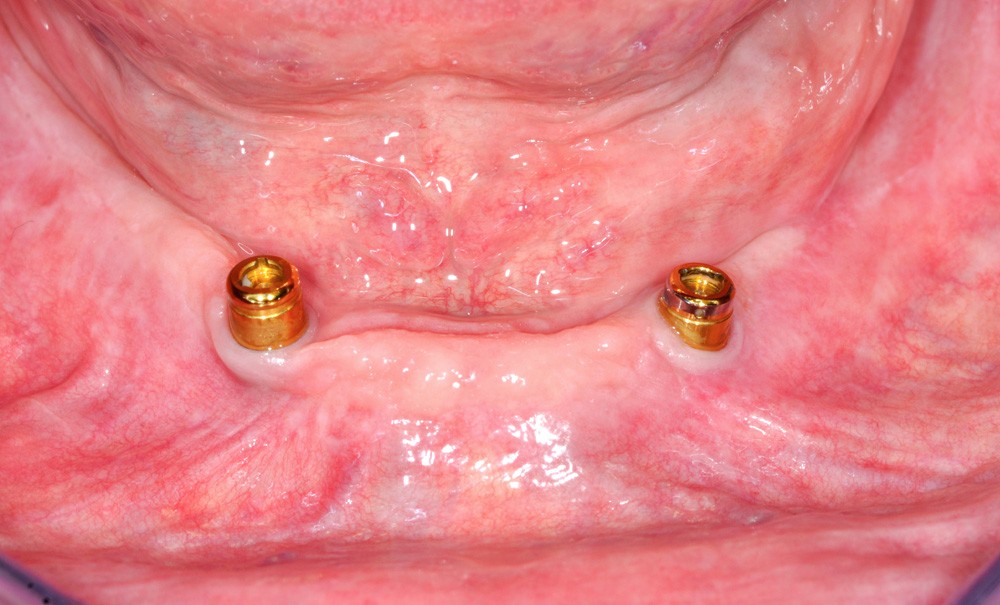

La prothèse amovible complète supra-implantaire (PACSI) mandibulaire est la thérapeutique de référence pour le traitement de l’édentement mandibulaire (McGill consensus, 2002, York consensus, 2008) [2]. Cette PACSI est implanto-retenue, car l’essentiel de la sustentation prothétique est assuré par la surface d’appui ostéo-fibro-muqueuse et les implants garantissent un complément de rétention par l’intermédiaire d’un système d’attachements [3]. Une grande variété de systèmes d’attachements existe, avec les barres et les attachements axiaux qui se déclinent en attachements magnétiques, attachements sphériques et attachements cylindriques. L’attachement cylindrique Locator (Sterngold) est le plus utilisé pour les motifs suivants : large diffusion chez les différentes firmes implantaires, facilité d’utilisation avec changement simple de l’attache en nylon, faible hauteur verticale pour les espaces prothétiques réduits, et maintenance relativement simple. Avec plus de 25 ans de recul clinique et un corpus important d’études scientifiques publié, le Locator s’est imposé comme la référence puisque, dans le langage courant, le terme « prothèse Locator » est utilisé pour désigner la PACSI. Les objectifs…